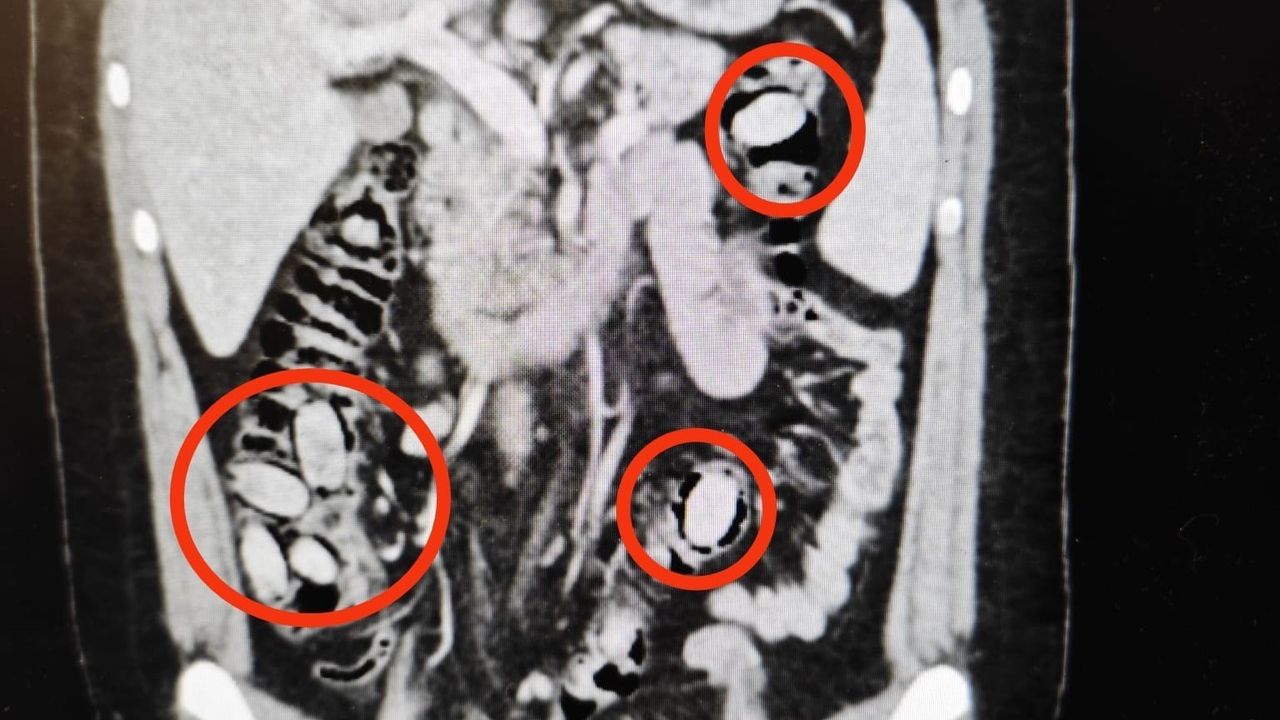

Yurtdışından Eskişehir'e gelen S.A. (25) isimli yabancı uyruklu şahsın kent girişindeki çevirme noktasında durumundan şüphelenilmesi üzerine hastanede yapılan detaylı tetkikler neticesinde yutmak suretiyle midesinde 44 kapsül metamfetamin maddesi taşıdığı anlaşıldı. Cerrahi müdahaleyle sözkonusu maddeler şahsın bedeninden çıkarıldı. Tedavisi akabinde şahıs tutuklandı. Yapılan titiz operasyon ile uyuşturucu maddelerin Eskişehir'de piyasaya sürülmeden ele geçirilmesi sağlandı.